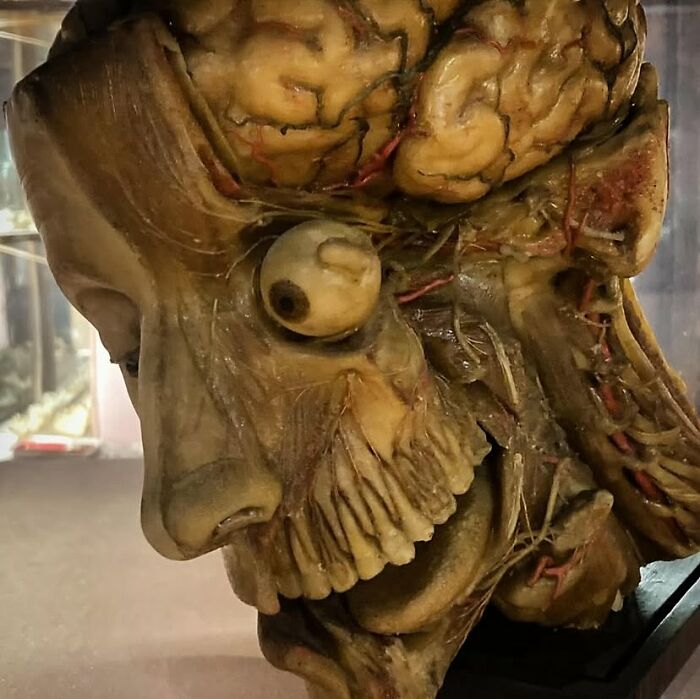

A wax model showing the anatomy of the head. It was produced in Naples by the sculptor Gennaro Ferrini between 1820 and 1830, with the wax modelled over a real skull.

Image credits: creepymedical